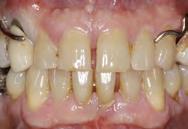

de 49 años de edad, el cual no refiere antecedentes patológicos y niega toxicomanías. Presenta falta de armonía oclusal y estética por pérdida de estructura dental por lesiones no cariosas en caras palatinas de órganos dentales anteriores superiores; asintomático. La línea de la sonrisa no es paralela a la línea interpupilar. Se le explicó ampliamente el motivo y el plan del estudio y firmó hoja de consentimiento válidamente informado.

Figura 4. Aspecto de los pilares después de la aplicación de la radiofrecuencia. Arco dentario superior e inferior.

Se presenta una paciente de 52 años la cual menciona que ya había recibido un tratamiento previo de ortodoncia que quedó inconcluso, actualmente todavía tiene los braquetes de ese tratamiento. Pero ahora ella quiere iniciar un nuevo tratamiento en el CESO con el fin de mejorar su mordida. Es diagnostica con clase II esquelética, de crecimiento hiperdivergente, biotipo dolicofacial, clase III canina y molar izquierda,

Figura 1. Frente y perfil. Figura 2. Lateral derecha, frente, izquierda de inicio.

clase III molar derecha, canino 13 retenido, mordida abierta, ausencia de los molares 26 y 46.

En las fotografías de inicio en la de frente (Figura 1) se observa la presencia de los brackets que todavía no han sido retirados y que son del tratamiento anterior, el perfil convexo.

Estudios de inicio intraorales

Las fotografías nos muestran en la Figura 2, la aparatología que se utilizó en el tratamiento que ella no terminó. La mordida abierta anterior de 1.5 mm, en la de frente las líneas medias no coincidentes, la clase III canina y molar izquierda, ausencia del canino 13 y del molar 46; en la Figura 3 el botón de Nance, algunos espacios en las arcadas.